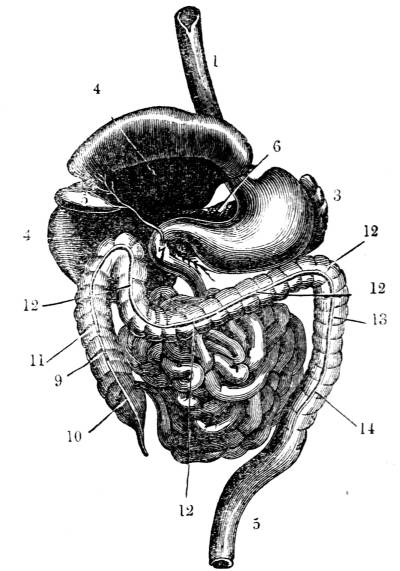

1. The trachea. 2. The right and left bronchus; the left

bronchus showing its division into smaller and smaller

branches in the lung, and the ultimate termination of the

branches in the air vesicles. 3. Right auricle of the heart.

4. Left auricle. 5. Right ventricle. 6. The aorta arising from

the left ventricle, the left ventricle being in this diagram

concealed by the right. 7. Pulmonary artery arising from

the right ventricle and dividing into, 8. The right, and

9. The left branch. The latter is seen dividing into smaller

and smaller branches, and ultimately terminating on the

air vesicles. 10. Branches of one of the pulmonary veins

proceeding from the terminations of the pulmonary artery

on the air vesicles, where together they form the net-work

of vessels termed the Rete Mirabile. 11. Trunk of the

vein on its way to the left auricle of the heart. 12.

Superior vena cava. 13. Inferior vena cava. 14. Air vesicles

magnified. 15. Blood-vessels distributed upon them.